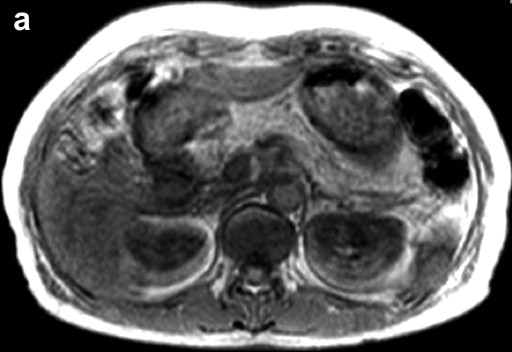

An esophagogastroduodenoscopy showed normal findings. Diseases such as reflux esophagitis and gastric ulcer were not observed. Ultrasonography (Figure 1) revealed a markedly heterogeneous pancreatic parenchyma demarcated from the neighboring tissues. The main pancreatic duct was not narrowed or dilated, and no tumor was detected. A CT image is shown in Figure 2. Plain CT (Figure 2a) revealed that the density of the pancreatic parenchyma had uniformly decreased to the same level as that of the surrounding fatty tissue. Contrast-enhanced CT (Figure 2b) revealed that the entire pancreatic parenchyma was absent and only a contrast-enhancing net-like shadow was visible. The magnetic resonance imaging (MRI) image is shown in Figure 3. The T1-weighted image could confirm that the entire pancreas was completely absent on T1-weighted images (fat suppression) (Figure 3). Endoscopic retrograde cholangiopancreatography (ERCP; Figure 4) showed no anomalous arrangement of the pancreaticobiliary ducts or pancreatic duct anomaly. Furthermore, obstruction, narrowing or dilatation of the main pancreatic duct was not observed. The branches of the pancreatic ducts appeared normal on the ERCP image. No abnormalities were observed in the bile duct.

Figure 3. Magnetic resonance imaging. a. T1-weighted image. b. T1-weighted image (fat suppression): the entire pancreas is completely absent. |